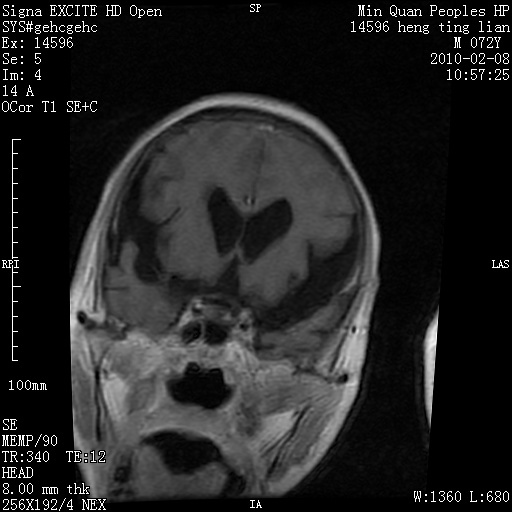

m,72,头疼,头晕两年,伴视力模糊三月,饮食呛咳两天。pe:颈部抵抗,左眼突出,左眼瞳孔约3mm,对光反射消失,双眼失明,伸舌困难,双肺呼吸音粗,心率110次/分,左上肢肌力i级,左下肢屈曲,肌张力高。现有08年2月19mri平扫及10年2月8日mri增强请会诊。ct病灶呈低密度伴散在点、片状等密度区,无明确钙化(无ct片资料可供上传)。[

脑外肿瘤,囊实性,环状不规则强化,内听道扩大,考虑神经源性肿瘤

左侧桥小脑区占位伴梗阻性脑积水----考虑 1神经鞘瘤 2室管膜瘤。

左侧桥小脑区神经鞘瘤伴梗阻性脑积水。

脑外肿瘤,病灶呈匍匐蔓延,表皮样囊肿可能性大。